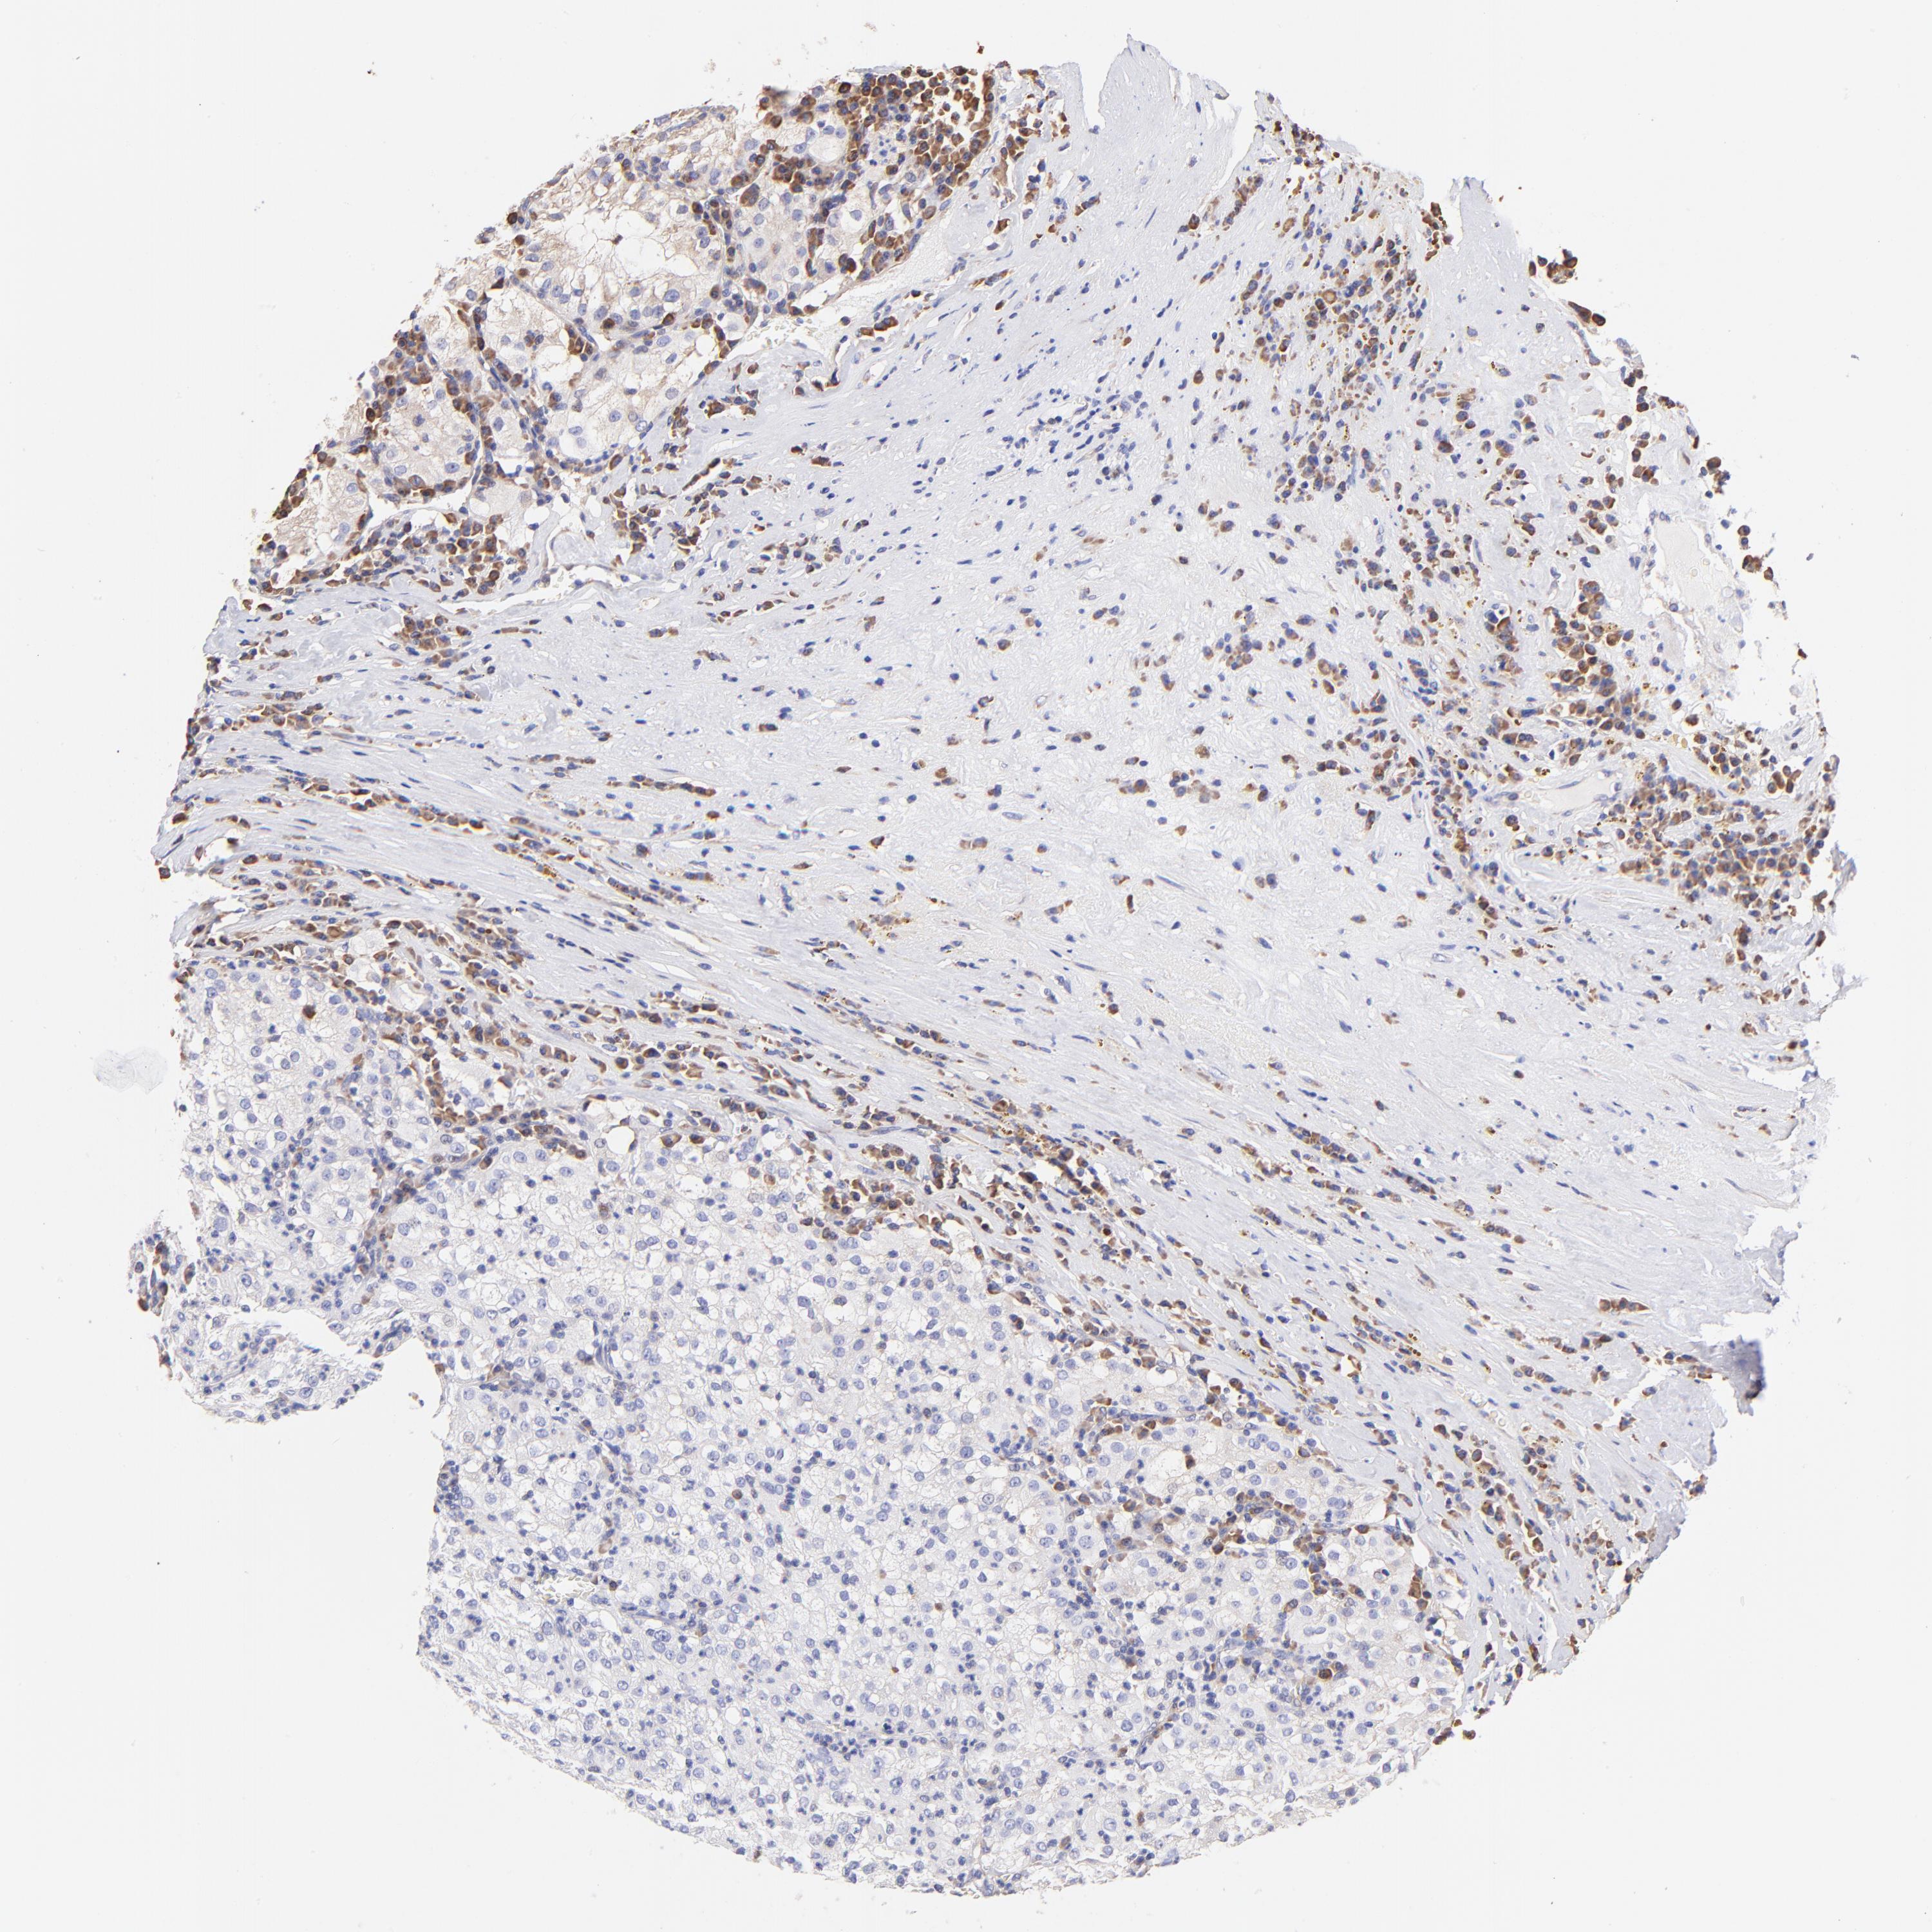

KIDNEY RENAL CLEAR CELL CARCINOMA (VALIDATION) - Interactive survival scatter ploti

The Survival Scatter plot shows the clinical status (i.e. dead or alive) for all individuals in the patient cohort, based on the same data that underlies the corresponding Kaplan-Meier plots. Patients that are alive at last time for follow-up are shown in blue and patients who have died during the study are shown in red.

The x-axis shows the expression levels (FPKM) of the investigated gene in the tumor tissue at the time of diagnosis. The y-axis shows the follow-up time after diagnosis (years). Both axes are complimented with kernel density curves demonstrating the data density over the axes. The top density plot shows the expression levels (FPKM) distribution among dead (red) and alive patients (blue). The right density plot shows the data density of the survived years of dead patients with high and low expression levels respectively, stratified using the cutoff indicated by the vertical dashed line through the Survival Scatter plot. This cutoff is automatically defined based on the FPKM cutoff that minimizes the p-score. The cutoff can be changed by dragging the vertical line or by entering a cutoff value in the square labeled "Current cut-off".

Under the Survival Scatter plot the p-score landscape (black curve; left axis) is shown together with dead median separation (red curve; right axis). Dead median separation is the difference in median mRNA expression between patients who have died with high and low expression, respectively. It is calculated as follows: median FPKM expression of dead patients with high expression - median FPKM expression of dead patients with low expression. This is intended to aid the user in visually exploring custom cutoffs and the associated p-scores and dead median separation.

Individual patient data is displayed and can be filtered by clicking on one or more of the category buttons on the top of the page. Categories describing expression level and patient information include: high, low, alive, dead, female, male and tumor stages. The scale of the x-axis can be toggled between linear and log-scale by clicking on the "x log" button. Mouse-over function shows TCGA ID, patient information and mRNA expression (FPKM) for each patient.

& Survival analysisi

Kaplan-Meier plots summarize results from analysis of correlation between mRNA expression level and patient survival. Patients were divided based on level of expression into one of the two groups "low" (under cut off) or "high" (over cut off). X-axis shows time for survival (years) and y-axis shows the probability of survival, where 1.0 corresponds to 100 percent.

RPL30 is not prognostic in Kidney Renal Clear Cell Carcinoma (validation)

Best expression cut offi

Based on the FPKM value of each gene, patients were classified into two groups and association between prognosis (survival) and gene expression (FPKM) was examined. The best expression cut-off refers the FPKM value that yields maximal difference with regard to survival between the two groups at the lowest log-rank P-value. Best expression cut-off was selected based on survival analysis .

When clicking on this number, the vertical dashed line indicating cut-off, the interactive survival plot, and the Kaplan-Meier curve will be adjusted to show results based on the best expression cut-off.

: 2107.92

TCGA RNA samplesi

RNA-seq data is reported as average FPKM (number Fragments Per Kilobase of exon per Million reads), generated by the The Cancer Genome Atlas (TCGA) .

Normal distribution across the dataset is visualized with box plots, shown as median and 25th and 75th percentiles. Points are displayed as outliers if they are above or below 1.5 times the interquartile range. FPKM values of the individual samples are presented next to the box plot.

Average pTPM 2524.7

Number of samples 100